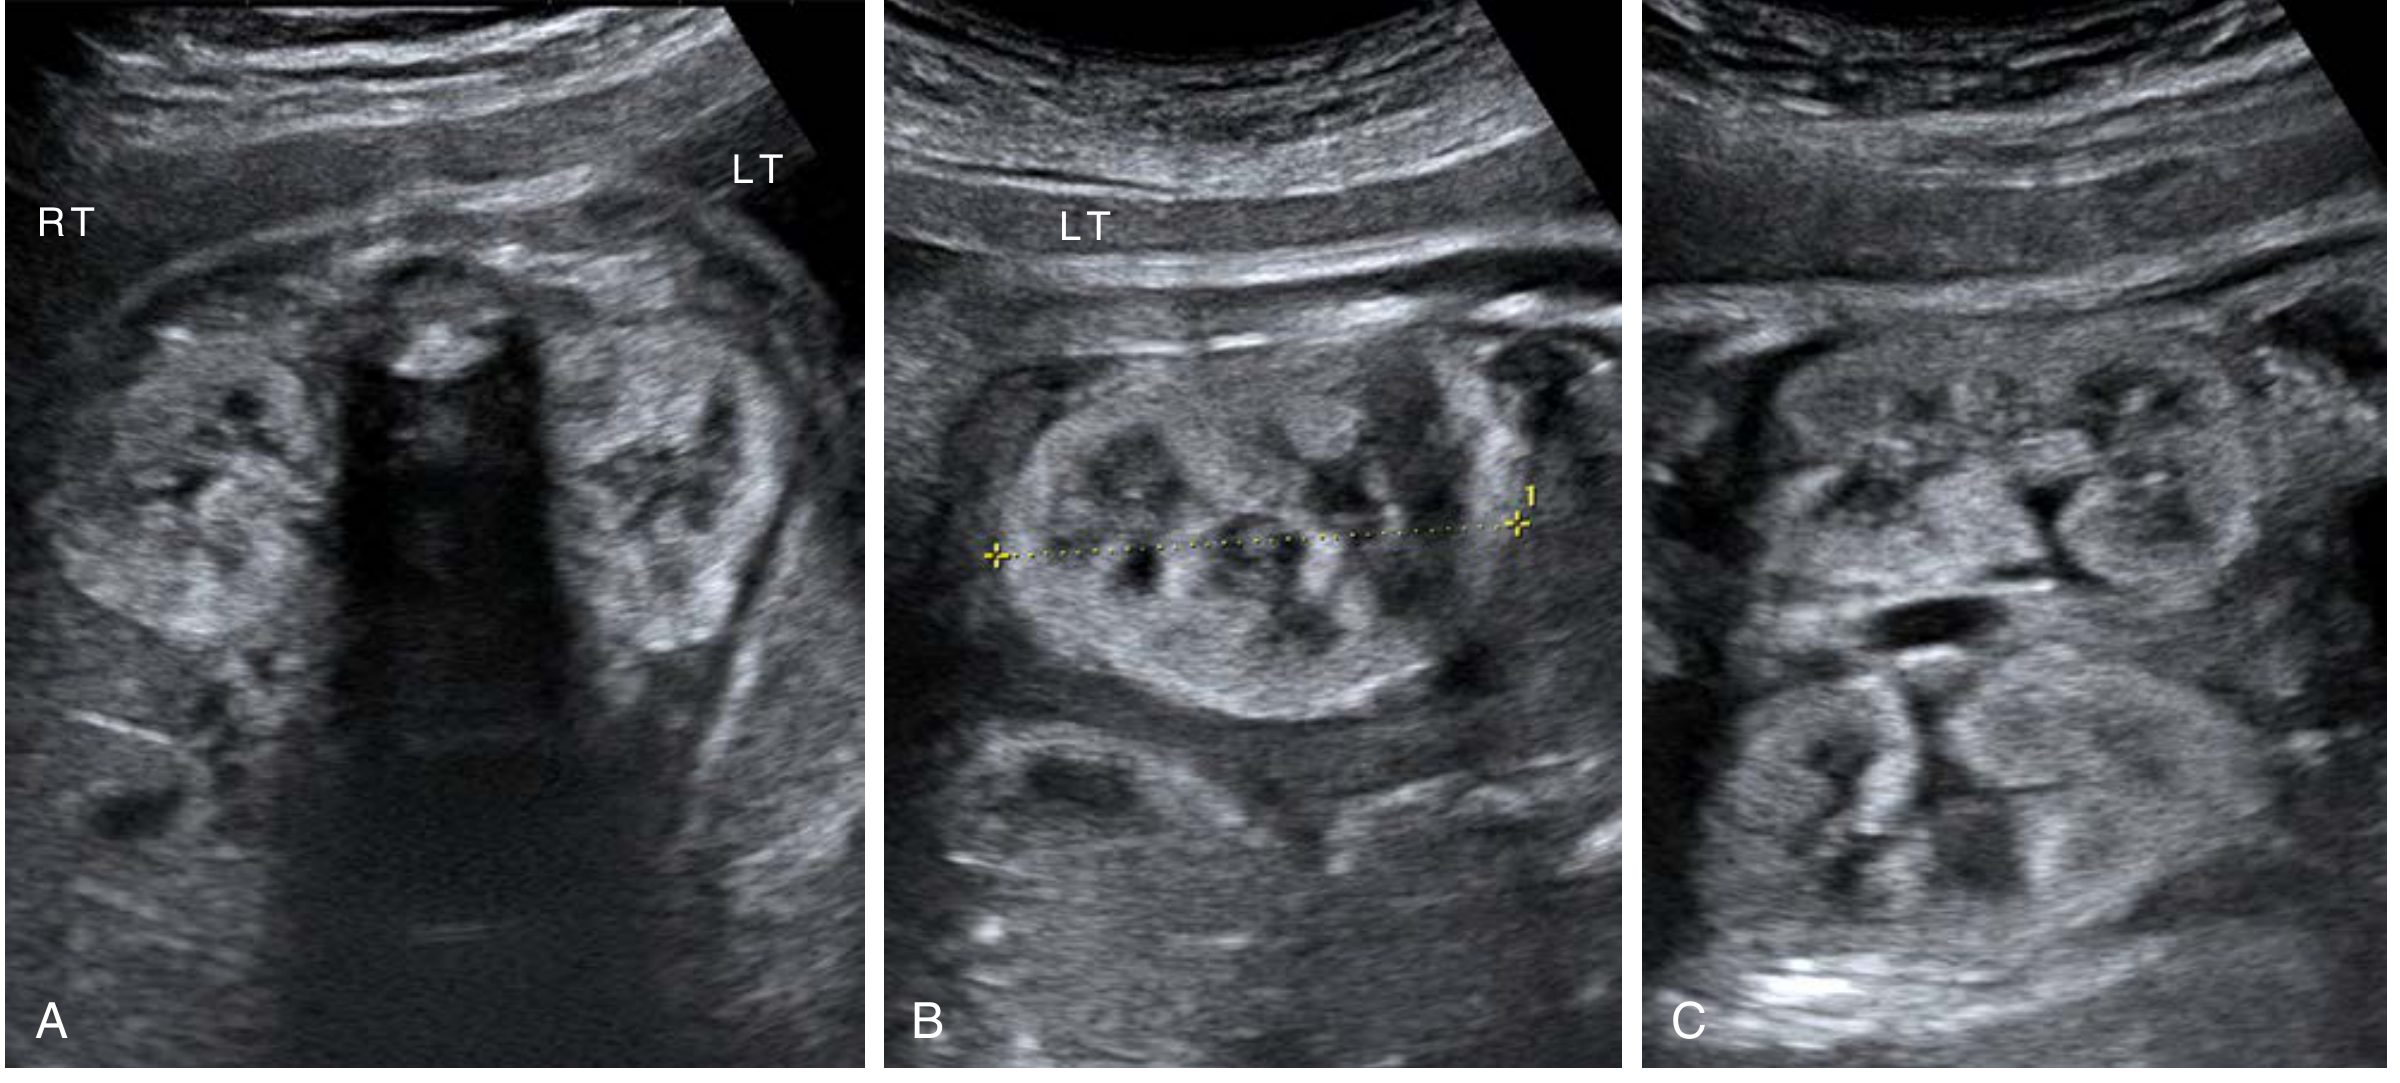

ARPKD — bilateral echogenic enlarged kidneys at 21 weeks with loss of corticomedullary differentiation and virtually no amniotic fluid

ARPKD at 21 weeks — bilateral enlarged echogenic kidneys with absent amniotic fluid (Creasy & Resnik's Maternal-Fetal Medicine)